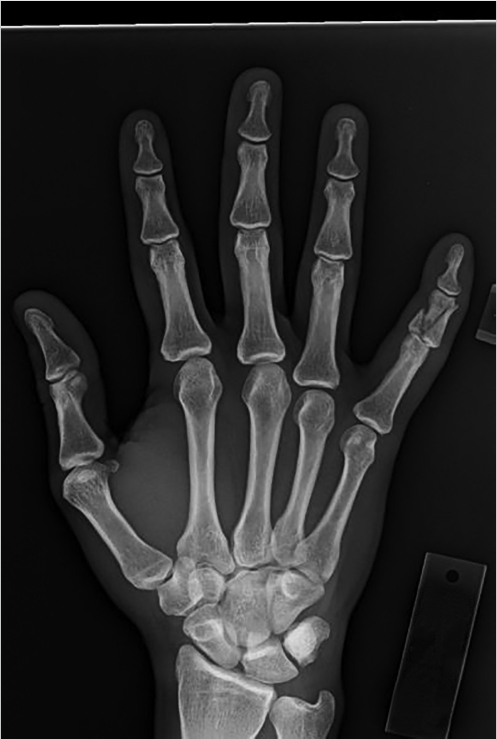

In the radiographic evaluation of hand fractures, plain radiographs are the mainstay of diagnosis. All hand injuries should be evaluated with anteroposterior (AP), lateral, and oblique radiographs. These three views are essential for visualizing the small bones in the hand to best characterize, and avoid missing, any fractures. In addition, it is best to order radiographs as specific to the injury as possible for the best view. For example, if the small finger has a deformity and a fracture is suspected, a three-view series of the small finger will yield higher quality images than a three-view series of the hand. This is because the sharpest images are obtained when the X-ray beam is centered over the area of interest; for example, hand series X-rays center the beam over the middle finger metacarpal which contrasts with dedicated finger series which center over the proximal phalanx. As a result, the AP image of a hand will capture the small finger slightly supinated potentially obscuring subtle fractures (Fig. 24‑2). In some injury patterns, additional radiograph views are useful, such as hook of the hamate view, navicular view, Robert’s view for a true AP view of the thumb, and dynamic studies such as the clenched fist view (Fig. 24‑3). 1 , 2 Computed tomography (CT) imaging is required only occasionally for fracture evaluation. Indications for CT imaging are primarily for operative planning in highly comminuted, intra-articular fractures. Magnetic resonance imaging is likewise rarely required for hand fractures, indicated mainly for detecting occult scaphoid fractures or early avascular necrosis such as in Kienbock’s disease. 2 While ultrasound imaging can be useful for soft-tissue hand injuries, it does not have utility in evaluating fractures.

When reading the radiographs, the treating physician should be able to accurately diagnose and describe the type of fracture sustained. This not only allows for determination of appropriate treatment but also ensures accurate and efficient communication with other physicians. Possible fracture patterns include transverse, oblique, spiral, and comminuted (Fig. 24‑4). Fractures are described by identifying the type of fracture, whether it is open or closed, commenting on the degree of comminution if present, the presence and direction of fracture fragment angulation, whether the fracture is apex-volar or apex-dorsal, whether there is any shortening or segmental loss of the overall bone length, measurement of any step-off of the fracture fragments, description of any rotational deformity, quantifying any articular surface involvement, and whether there is any associated joint dislocation (Fig. 24‑5).